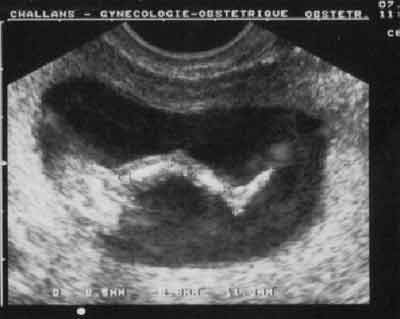

Membres inférieurs : 3 segments